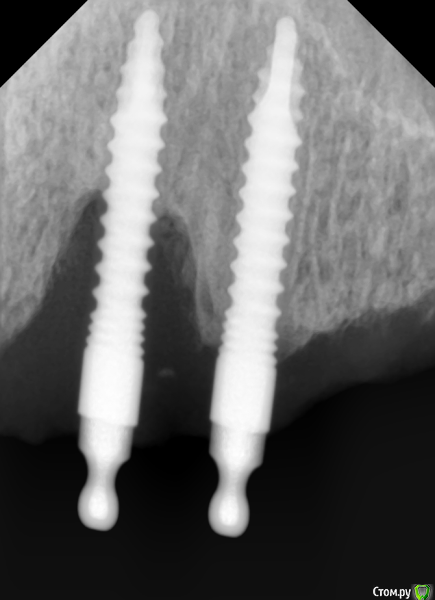

Sergiosse Опубликовано 14 июня, 2016 Поделиться Опубликовано 14 июня, 2016 (изменено) Не знаю как добавить фото в ранее созданую тему, поэтому создал новую.3 года назад установлены 4 цельных импланта остем для фиксации ПСП на в.ч. Сейчас на плановом осмотре импланты стабильны,жалоб нет в обл. 15 импланта свищь с отделяемым,н а снимке вертикальный очаг деструкции на 2/3 длинны импланта.С импл. в обл. 14 все окей. Гигиена отличная,использует ирригатор. Промыл хлоргексидином. Какая дальнейшая тактика? В чем причина.с нимок выложу позже. Изменено 14 июня, 2016 пользователем Sergiosse Ссылка на комментарий